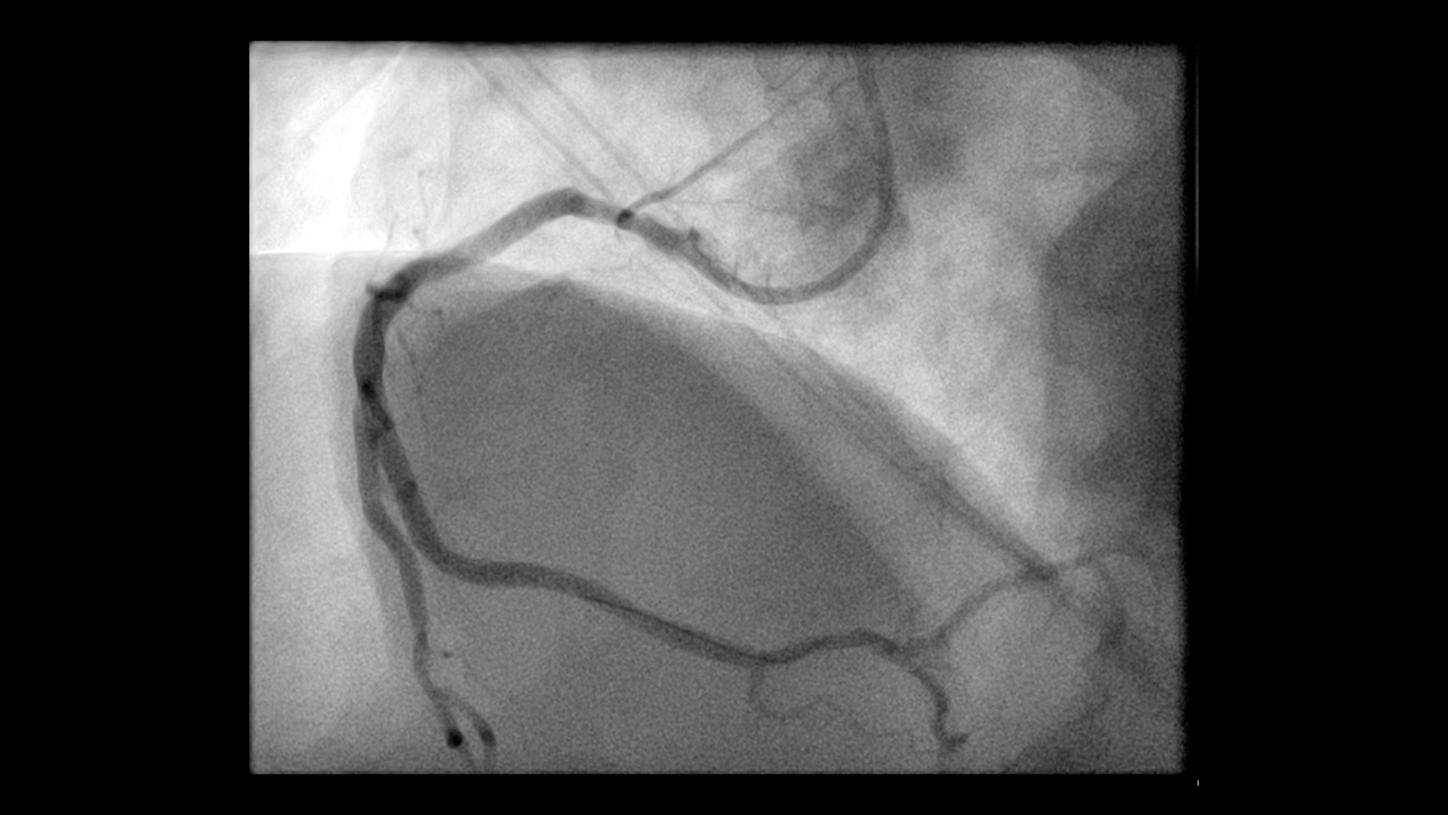

During minimally invasive procedures, it is critical to have a clear view of anatomies and devices. Yet complex imaging tasks or challenging patient conditions often impact image quality. OPTIQ AI delivers constant image quality1 defined by CNR in support of the ALARA principle, independent of patient or C-arm angulation. On top, an AI-powered algorithm reduces image noise in real time across different 2D imaging modes.

Make AI-powered imaging and clear insights your standard during interventions – with OPTIQ AI.